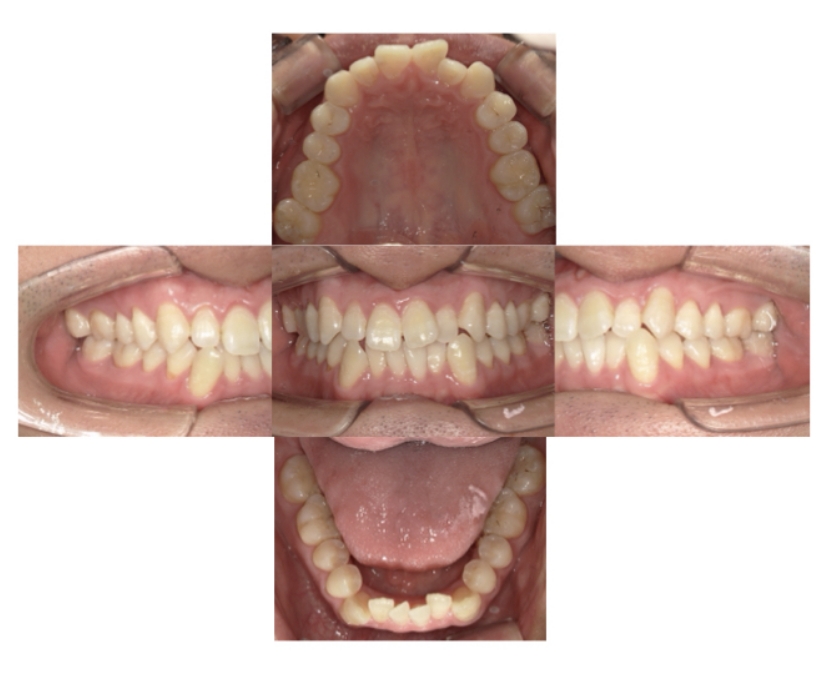

BEFORE

AFTER

上下顎叢生、上顎前突(出っ歯、上下の前歯のガタガタ)のケースです。

装置はラビアル(上下表側)で、上顎の小臼歯を2本抜歯を行っています。抜歯したスペースを使って、上の前歯の後方移動と叢生(ガタガタ)と出っ歯の改善を行っています。下は歯と歯の間にIPR(隣接面削合)を行い、スペースを確保し、叢生の改善を行っています。

主訴 前歯のガタガタと出っ歯が気になる。

年齢・性別 47歳 女性

治療方針 抜歯スペースおよびIPRを利用して上前歯の叢生(ガタガタ)の改善

抜歯部位 上顎左右第一小臼歯

使用装置 ラビアル(上下表側)、顎間ゴム

治療期間 2年0か月